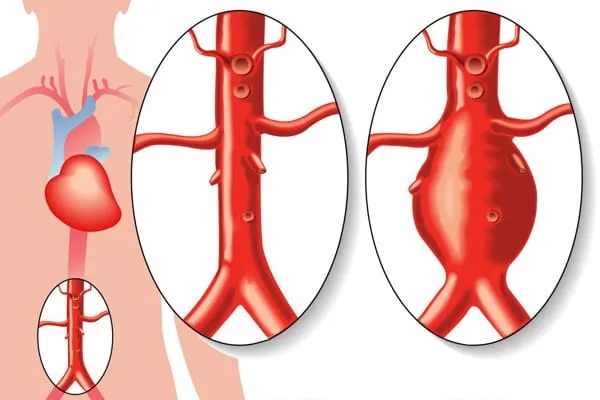

Repeated arterial compression in the thoracic outlet causes local damage to the subclavian artery. This damage may involve only the inner arterial wall, causing arterial scarring or stenosis (focal narrowing). However, if the damage involves the full thickness of the arterial wall, an aneurysm may develop. An aneurysm is a bulging or ballooning of the artery, with focal increased diameter of the artery.

Development of arterial aneurysm in the abdominal aorta